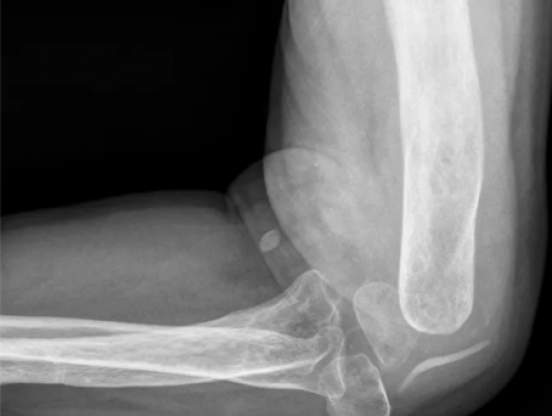

• 肘关节置换治疗伴伸肘功能障碍的肘外伤后遗症1例

吴岩

浙江大学医学院附属第二医院